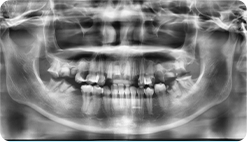

Sau khi chụp X-quang và quan sát trực tiếp,

răng của Ngân đang gặp các vấn đề nghiêm trọng

Hàm trên mất 2 răng do tai nạn giao thông, và 2 năm sau, chân của 2 răng bị lủng, gãy

8 răng bị hư cần điều trị tủy: Răng số 15, 12, 21, 22, 25, 31, 41, 45

Hàm dưới 10 chân răng bị hư nặng, mất chân răng, cần phải nhổ răng số 11, 17, 16, 25, 27, 26, 37, 38, 46, 47

Gớm xoang thấp, cần điều trị nâng xoang